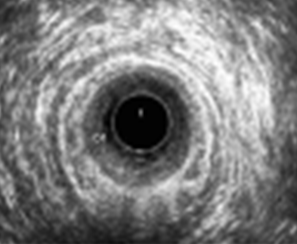

Ενδοπρωκτικό υπερηχογράφημα – Διήθηση πρωκτικού σωλήνα από το νεόπλασμα. Ευγενική παραχώρηση Dr. V. Penopoulos.